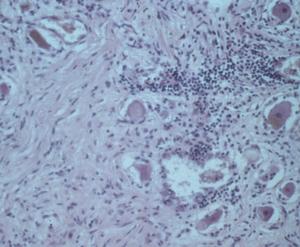

Another pattern seen in Lyme arthritis/synovitis is hypertrophic villous synovitis, a non-specific histologic lesion seen in other oligoarthritides, including undifferentiated arthritis. Here, the synovial surface is folded into fronds, yielding a villous appearance. Synovial surface cells are either of normal thickness or can thicken to 5-6 cells. The stroma of the villi demonstrate vascular proliferation (angiogenesis) to a degree that simulates a capillary hemangioma. Plasma cells are found in abundance in Lyme synovitis and are associated with large numbers of Giemsa stain-positive tissue mast cells.

Late disseminated infection of the skin is called acrodermatitis chronica atrophicans and occurs mainly in Europe. Histopathology in these cases is characterized by transdermal, comparatively dense and diffuse mononuclear inflammatory cells, including plasma cells, in association with dilated lymphatics (Fig. 6). The degree of these findings varies from case to case, but dermal inflammation is significantly greater than that of erythema migrans. Spirochetes can be demonstrated in many of these pathologic lesions except recurrent synovitis, which may be a molecular cross-reactive phenomenon. Spirochetes are always difficult to demonstrate in patients who have had prior or concurrent antibiotic therapy.